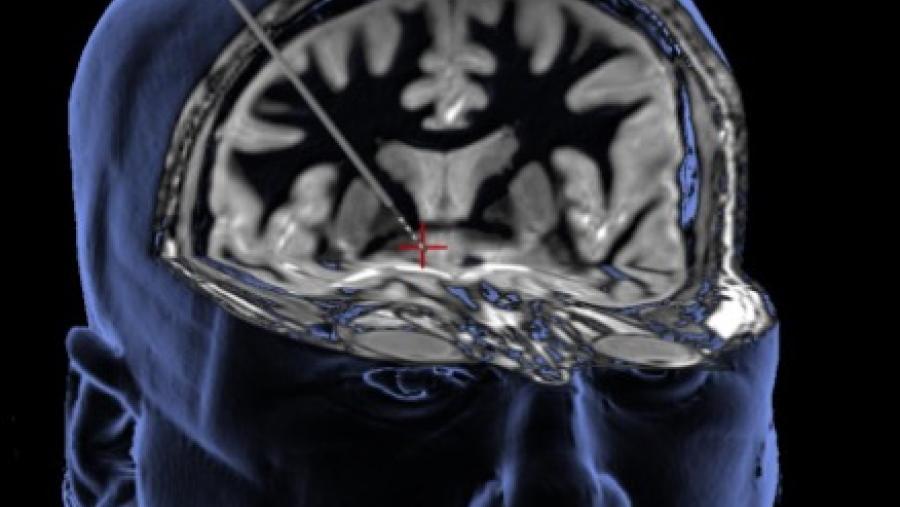

Image

Can resetting brain circuits help people find recovery?

Published: November 15, 2022

Topics:

Drug Development